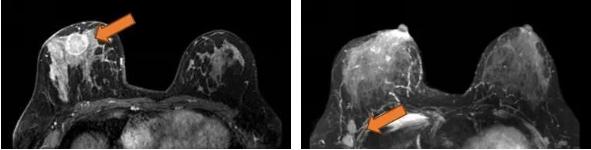

2021.7.7乳腺MRI: 右乳外上象限肿物(BI-RADS-6)3.1cm×1.9cm×3.0cm,右腋窝见肿大淋巴结,M灶可能。

右乳外上象限见不规则肿块,呈长/稍长T2、等T1信号,DWI呈高信号,ADC图信号减低,ADC值约0.863,增强扫描明显强化,TIC呈Ⅲ型,大小约3.1×1.9×3.0cm,邻近皮肤增厚,皮下脂肪层模糊,另肿块外侧旁见小肿块影,增强明显强化,与外上象限肿块相连。右侧腋窝见肿大淋巴结。

图3. 乳腺MRI

(3 cycle 后)2021.9.22 复查乳腺MRI示:右乳肿块较前减小14mm×9mm×18mm。

图7. 乳腺MRI